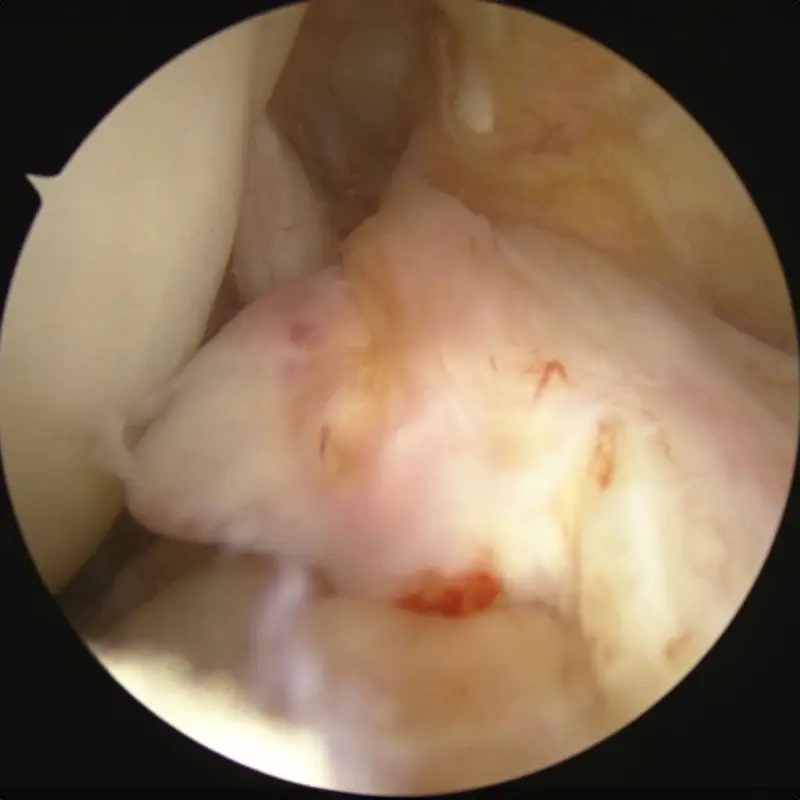

Appearance of torn ACL, good stump appropriate for BEAR procedure.